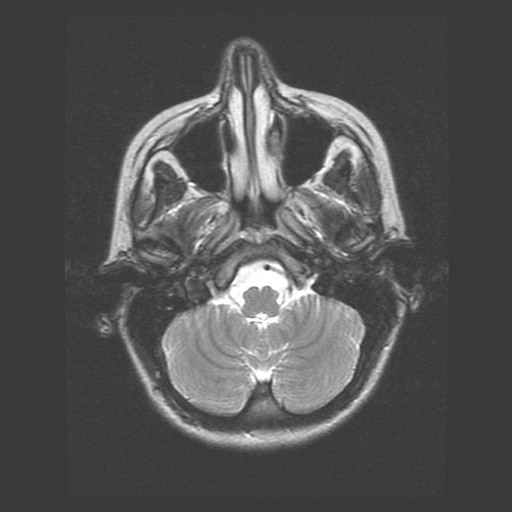

Schedel